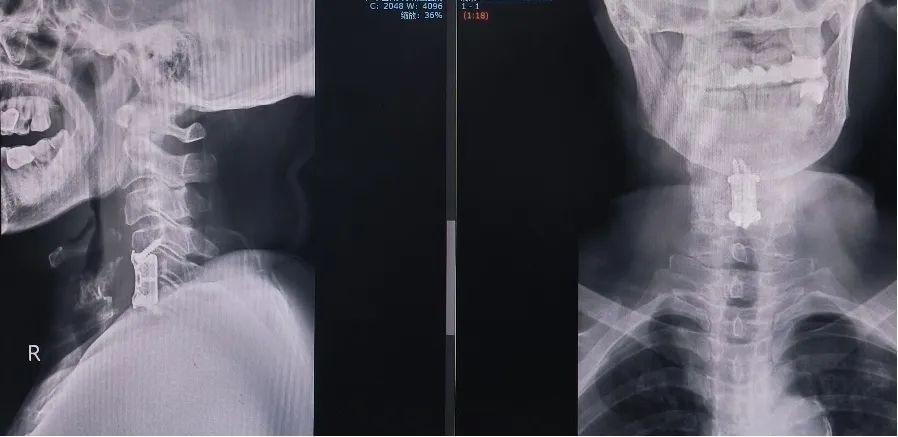

术后复查